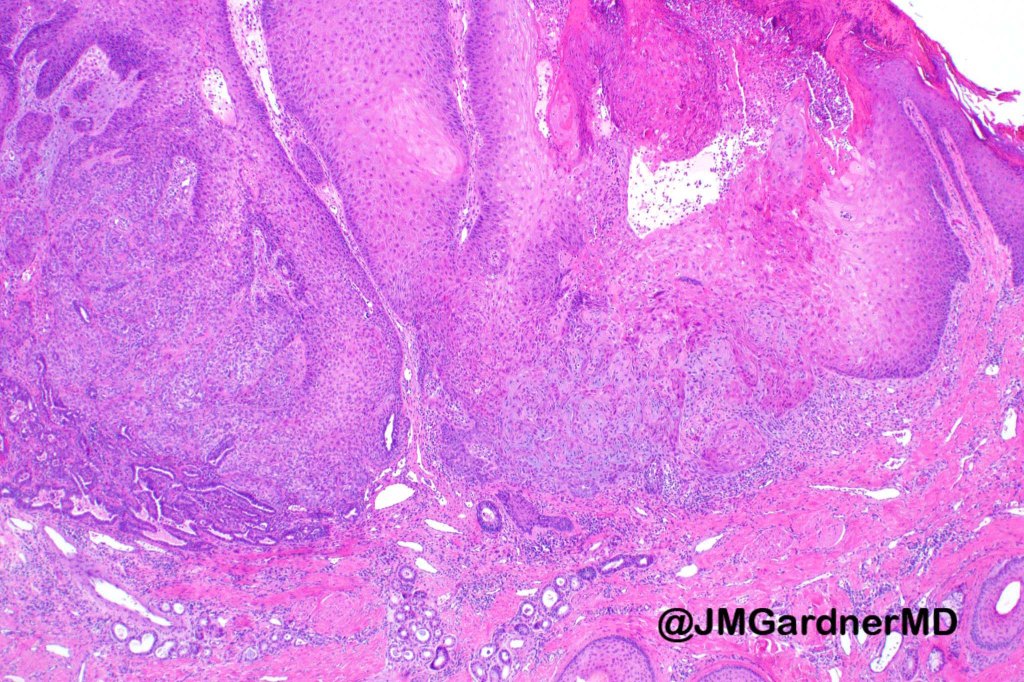

•Scanning magnification shows an exophytic tumor or an epidermal invagination enclosing epithelial covered papillae with a fibrovascular core

•Glands are present at the base of the lesion

•At the edges, the squamous epithelium is in continuity with the glandular one

•The epithelium consists of outer myoepithelial cells supporting an inner layer of columnar cells with abundant eosinophilic cytoplasm showing decapitation secretion

•Dense plasma cell infiltrate